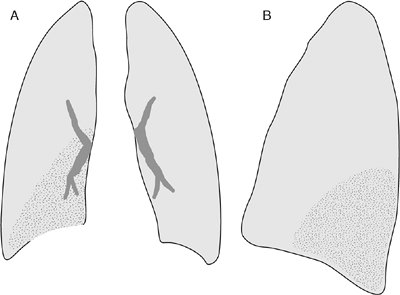

FIGURE 11-7. Right middle lobe atelectasis. A: Frontal view of the chest shows loss of the right heart border and an ill-defined area of increased opacification in the right medial lung (stippled area). B: Lateral view shows triangular area of opacification (black area) overlying the heart, with approximation of the minor and major fissures. (Reprinted with permission from

Collins J. 1996 Joseph E. Whitley, MD, Award. Evaluation of an introductory course in chest radiology. Acad Radiol. 1996;3:994–999.

)